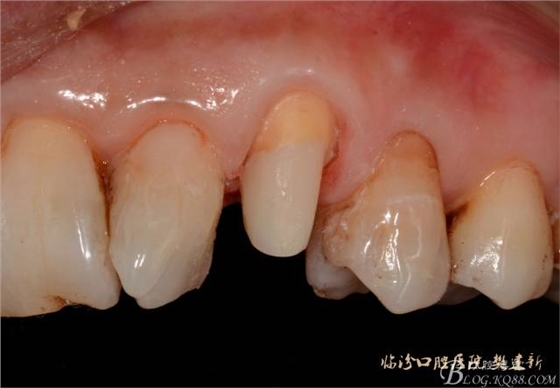

口內(nèi)檢查: 23殘根,位于齦上3MM,根管口探無反應(yīng),叩(+-),無松動,牙周無紅腫.X片示:23根管無阻射,根尖骨密度降低.11.12.13頸部楔形缺損,探敏感,牙髓活力正常.全口牙結(jié)石色素(+).

圖123口內(nèi)修復(fù)前情況:殘根位于齦上3MM,牙周無紅腫.